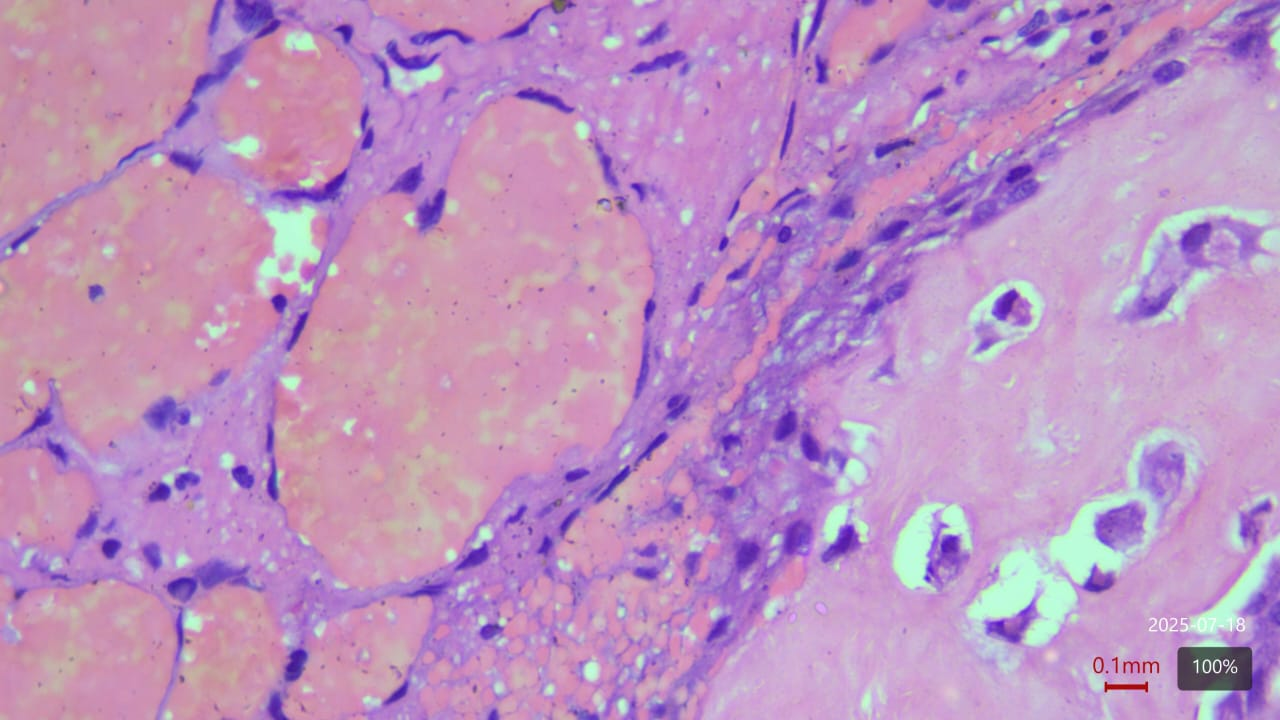

Histopathology

Biopsies demonstrated benign vascular channels lined by flattened endothelial cells with no atypia or malignant transformation. Despite the benign appearance, radiological progression persisted (Fig 8).

Figure 8